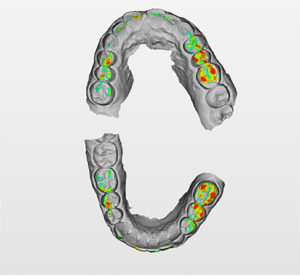

Lors de cette première consultation, en plus de l’examen clinique, on réalise une empreinte optique (Fig.2).

Fig.2.

Elle a deux buts. Le premier relève de la communication : il est plus facile pour la patiente de se rendre compte de l’état d’usure de ses dents avec une image 3D en plus des photographies et du miroir de courtoisie. Le deuxième but est l’analyse de l’occlusion. Grâce au logiciel d’exploitation (ici, Dexis IS Scan Flow), on se rend bien compte que l’occlusion est serrée avec des contacts extrêmement forts à droite (en rouge sur le Scan Flow). Il est alors facile de conclure et d’expliquer dès à présent à la patiente qu’il est impossible de restaurer son sourire dans cette situation occlusale. Pour redonner de la hauteur aux dents antérieures il faut de la place, créée soit par soustraction en préparant les dents antérieures, soit par addition en relevant la hauteur des dents postérieures. La patiente fait rapidement son choix. Pour nous, cela signifie qu’il va falloir augmenter la DVO.